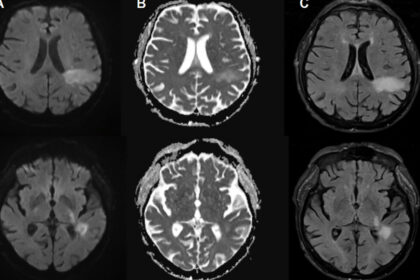

Vous êtes probablement déjà infecté par un virus mangeur de cerveau dont vous n’avez jamais entendu parler Il existe un virus dont la plupart des gens n’ont jamais entendu parler, mais qui...